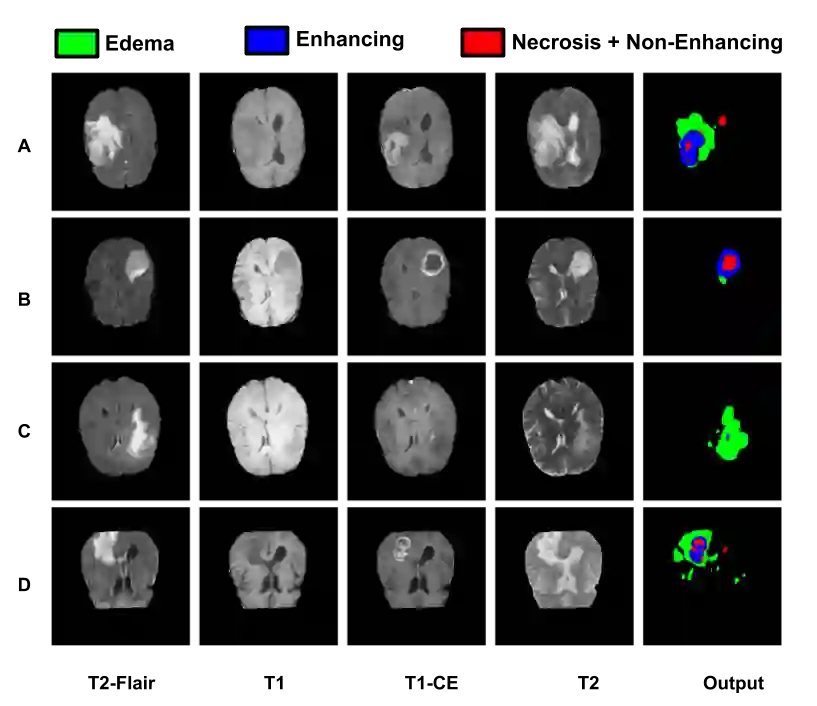

Gliomas are one of the most frequent brain tumors and are classified into high grade and low grade gliomas. The segmentation of various regions such as tumor core, enhancing tumor etc. plays an important role in determining severity and prognosis. Here, we have developed a multi-threshold model based on attention U-Net for identification of various regions of the tumor in magnetic resonance imaging (MRI). We propose a multi-path segmentation and built three separate models for the different regions of interest. The proposed model achieved mean Dice Coefficient of 0.59, 0.72, and 0.61 for enhancing tumor, whole tumor and tumor core respectively on the training dataset. The same model gave mean Dice Coefficient of 0.57, 0.73, and 0.61 on the validation dataset and 0.59, 0.72, and 0.57 on the test dataset.